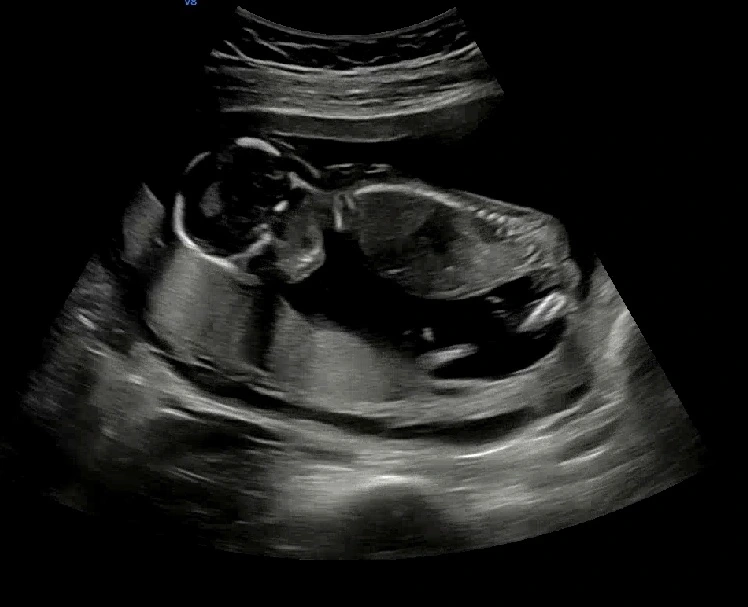

임신 16주차 초음파

아기는 잘 자라고 있었다. 나는 그저 잘 먹고 잘 자기만 했을 뿐인데 아기는 어느덧 이렇게 자라있었다. 우와… 예비 엄마로서 이런 말 하기 부끄럽지만 이때부터 내 뱃속에 정말 아기가 있었구나, 게다가 무럭무럭 잘 자라고 있구나 하고 정말 크게 느꼈다. 그저 신기하기만 해요…!!

성별을 알려주신다고 했는데 아기가 가리고 있어서 다음에 다시 알려주시겠다고 … ^^ 한 달 후에 오라고 하셨는데 그때까지 어떻게 기다리지? ㅎㅎㅎ